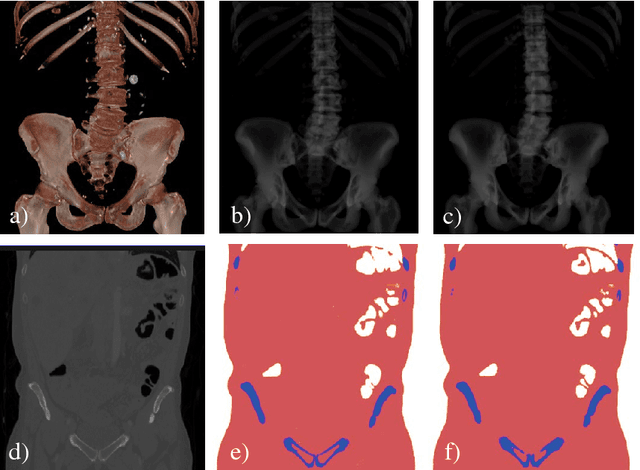

Abstract:Machine learning-based approaches outperform competing methods in most disciplines relevant to diagnostic radiology. Interventional radiology, however, has not yet benefited substantially from the advent of deep learning, in particular because of two reasons: 1) Most images acquired during the procedure are never archived and are thus not available for learning, and 2) even if they were available, annotations would be a severe challenge due to the vast amounts of data. When considering fluoroscopy-guided procedures, an interesting alternative to true interventional fluoroscopy is in silico simulation of the procedure from 3D diagnostic CT. In this case, labeling is comparably easy and potentially readily available, yet, the appropriateness of resulting synthetic data is dependent on the forward model. In this work, we propose DeepDRR, a framework for fast and realistic simulation of fluoroscopy and digital radiography from CT scans, tightly integrated with the software platforms native to deep learning. We use machine learning for material decomposition and scatter estimation in 3D and 2D, respectively, combined with analytic forward projection and noise injection to achieve the required performance. On the example of anatomical landmark detection in X-ray images of the pelvis, we demonstrate that machine learning models trained on DeepDRRs generalize to unseen clinically acquired data without the need for re-training or domain adaptation. Our results are promising and promote the establishment of machine learning in fluoroscopy-guided procedures.